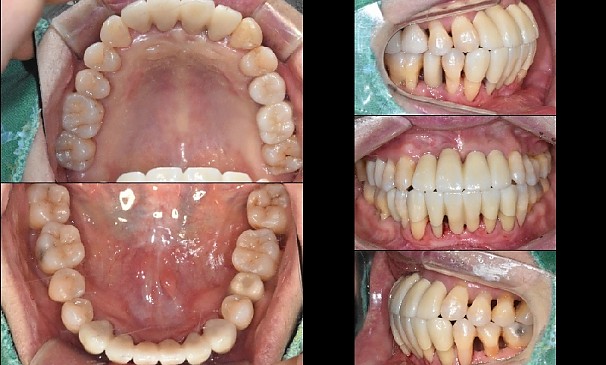

박OO님 전후사진 | 치료 기간 : 30

치료 후